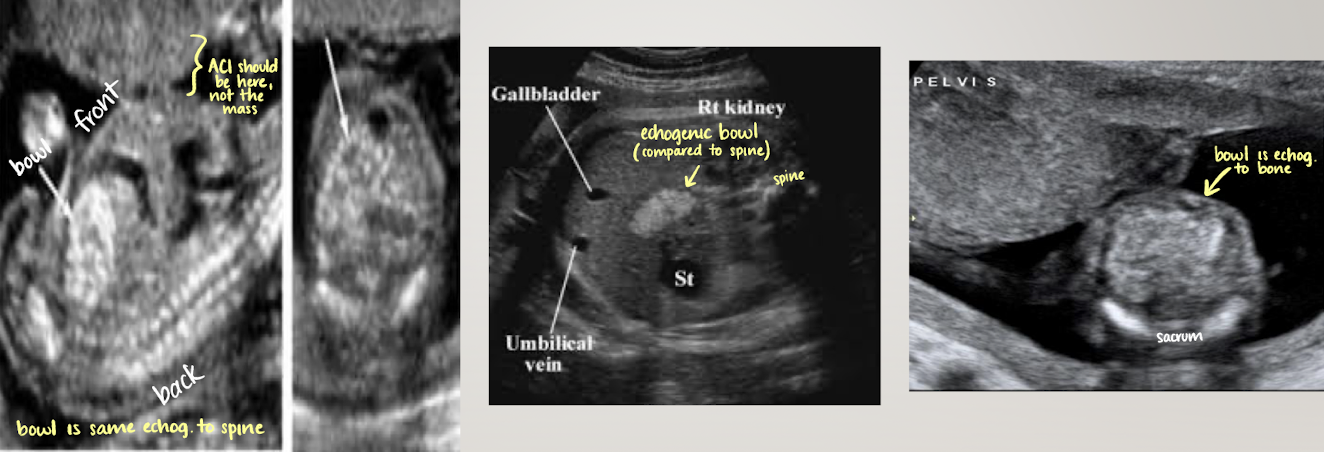

small bowel

mid-lower abdomen; centrally located echogenic areas inferior to liver

SONO: varies with menstrual age

mid gut herniation (<12wks)

early pregnancy=hypoechoic

late pregnancy=more echogenic

hyperechoic bowel is NOT normal

echogenicity should always be less than bone

may see peristalsis in 3rd trimester (normal)

large bowel

seen after 22w (can discern between small and large)

more peripherally than small bowel

hypoechoic tubular structure (meconium)

meconium=baby stool

well-defined walls

haustral folds appear as thin linear echoes within lumen

gallbladder

seen after 20 weeks

SONO: elongated anechoic structure in long-axis; circle in short-axis

in right abdomen near liver

more oval than intrahepatic umbilical vein

document presence

abdominal cord insertion (ACI)

becomes belly button after born

umbilical cord seen entering fetal abdomen just above level of bladder

UV courses to liver within falciform ligament

ensure smooth abdominal cord insertion (should be nothing “pooching” out)

rule out gastroschisis and omphalocele

gastroschisis

“loose bowel pooching out—floating outside abdomen”

omphalocele

bowl or other organs come out, BUT difference is… it will be encased in a membrane

looks like a contained mass with smooth borders b/c of membrane